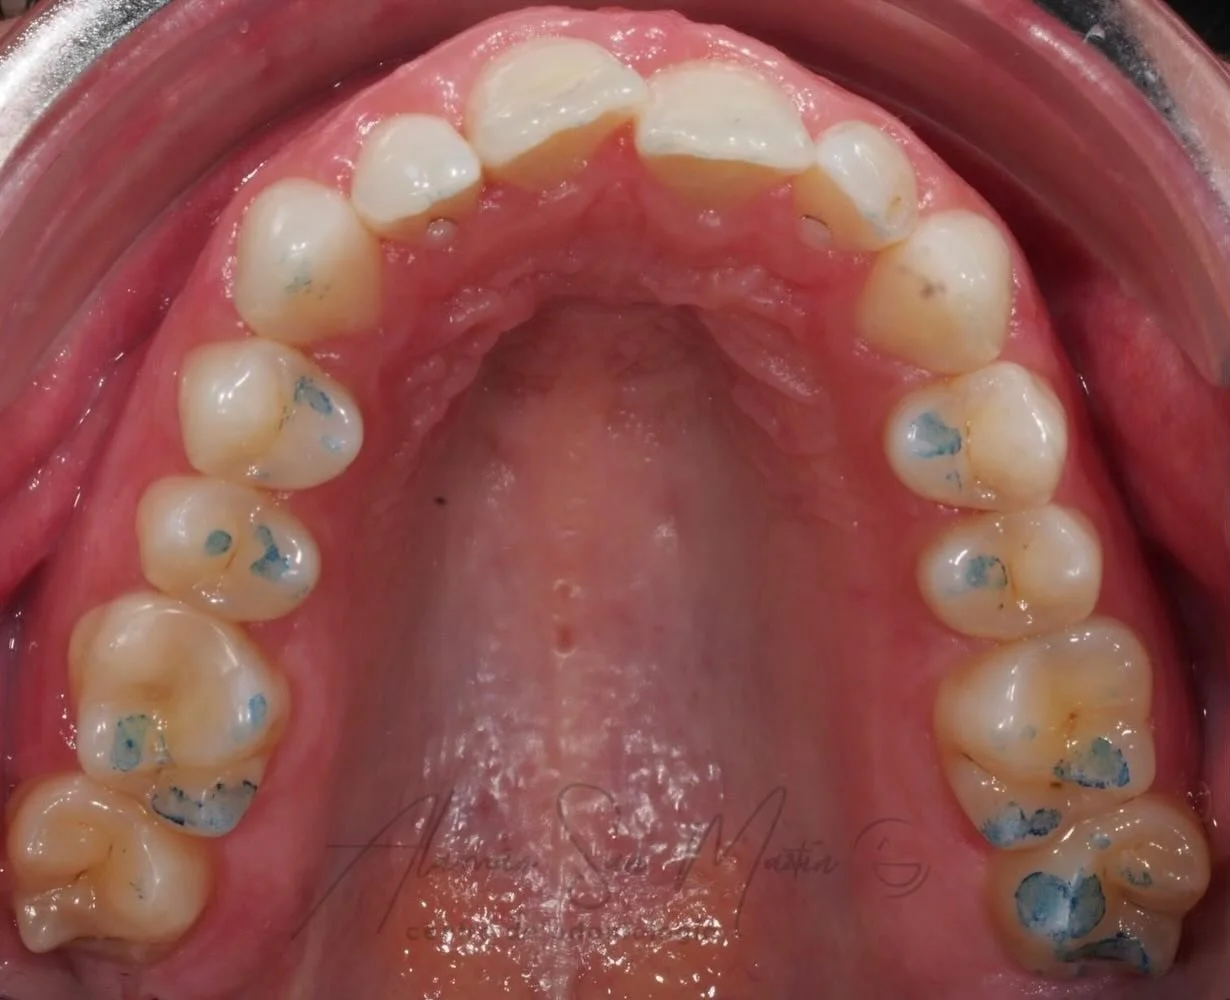

Aplicamos las últimas novedades y técnicas de Blanqueamiento Dental para conseguir cambios realmente notables en el aclaramiento del color de los dientes sin daño alguno para el paciente.

Antes del blanqueamiento se evalúa el estado de los dientes y se toman registros valorando el color inicial y la indicación del tratamiento.

Pueden realizarse sesiones de Blanqueamiento en Clínica incluso con Lámpara de Blanqueamiento, combinándolas después con un Blanqueamiento en casa con cubetas que se colocan sobre los dientes un número de horas al día.